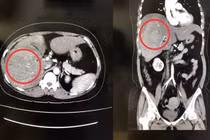

Dùng dây đai nịt bụng để giảm cân, người phụ nữ bị vỡ gan Đời sống 247 23/02/2023 15:07 Nữ bệnh nhân 39 tuổi nhập viện với tình trạng vỡ gan, chảy máu ổ bụng do sử dụng dây đai nịt bụng để giảm cân trong thời gian dài